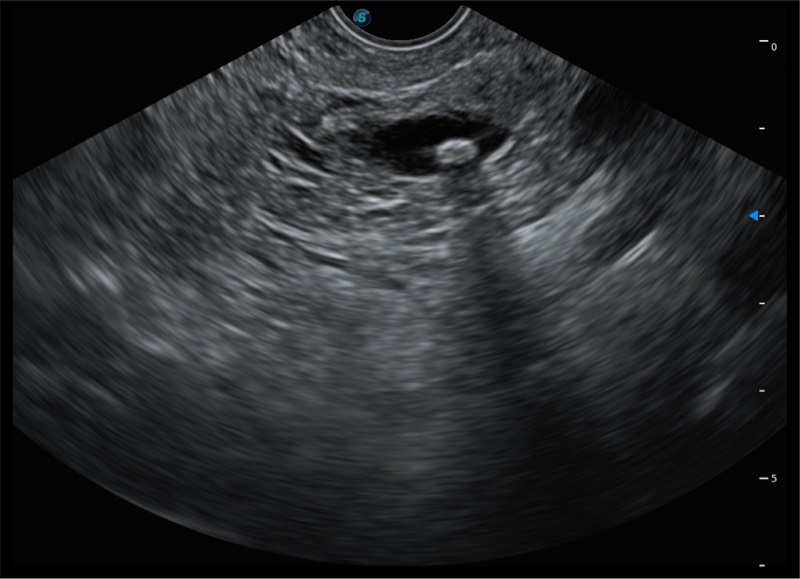

基于二十年的超声技术积累,九州酷游提供了最新一代的独立超声主机,在提供高质量图像的同时满足多学科使用。具备常见多普勒技术并提供弹性成像、声学造影等高端影像技术。新一代传感器具有更强的抗干扰能力并减少图像伪影。

150°超声扫描角度